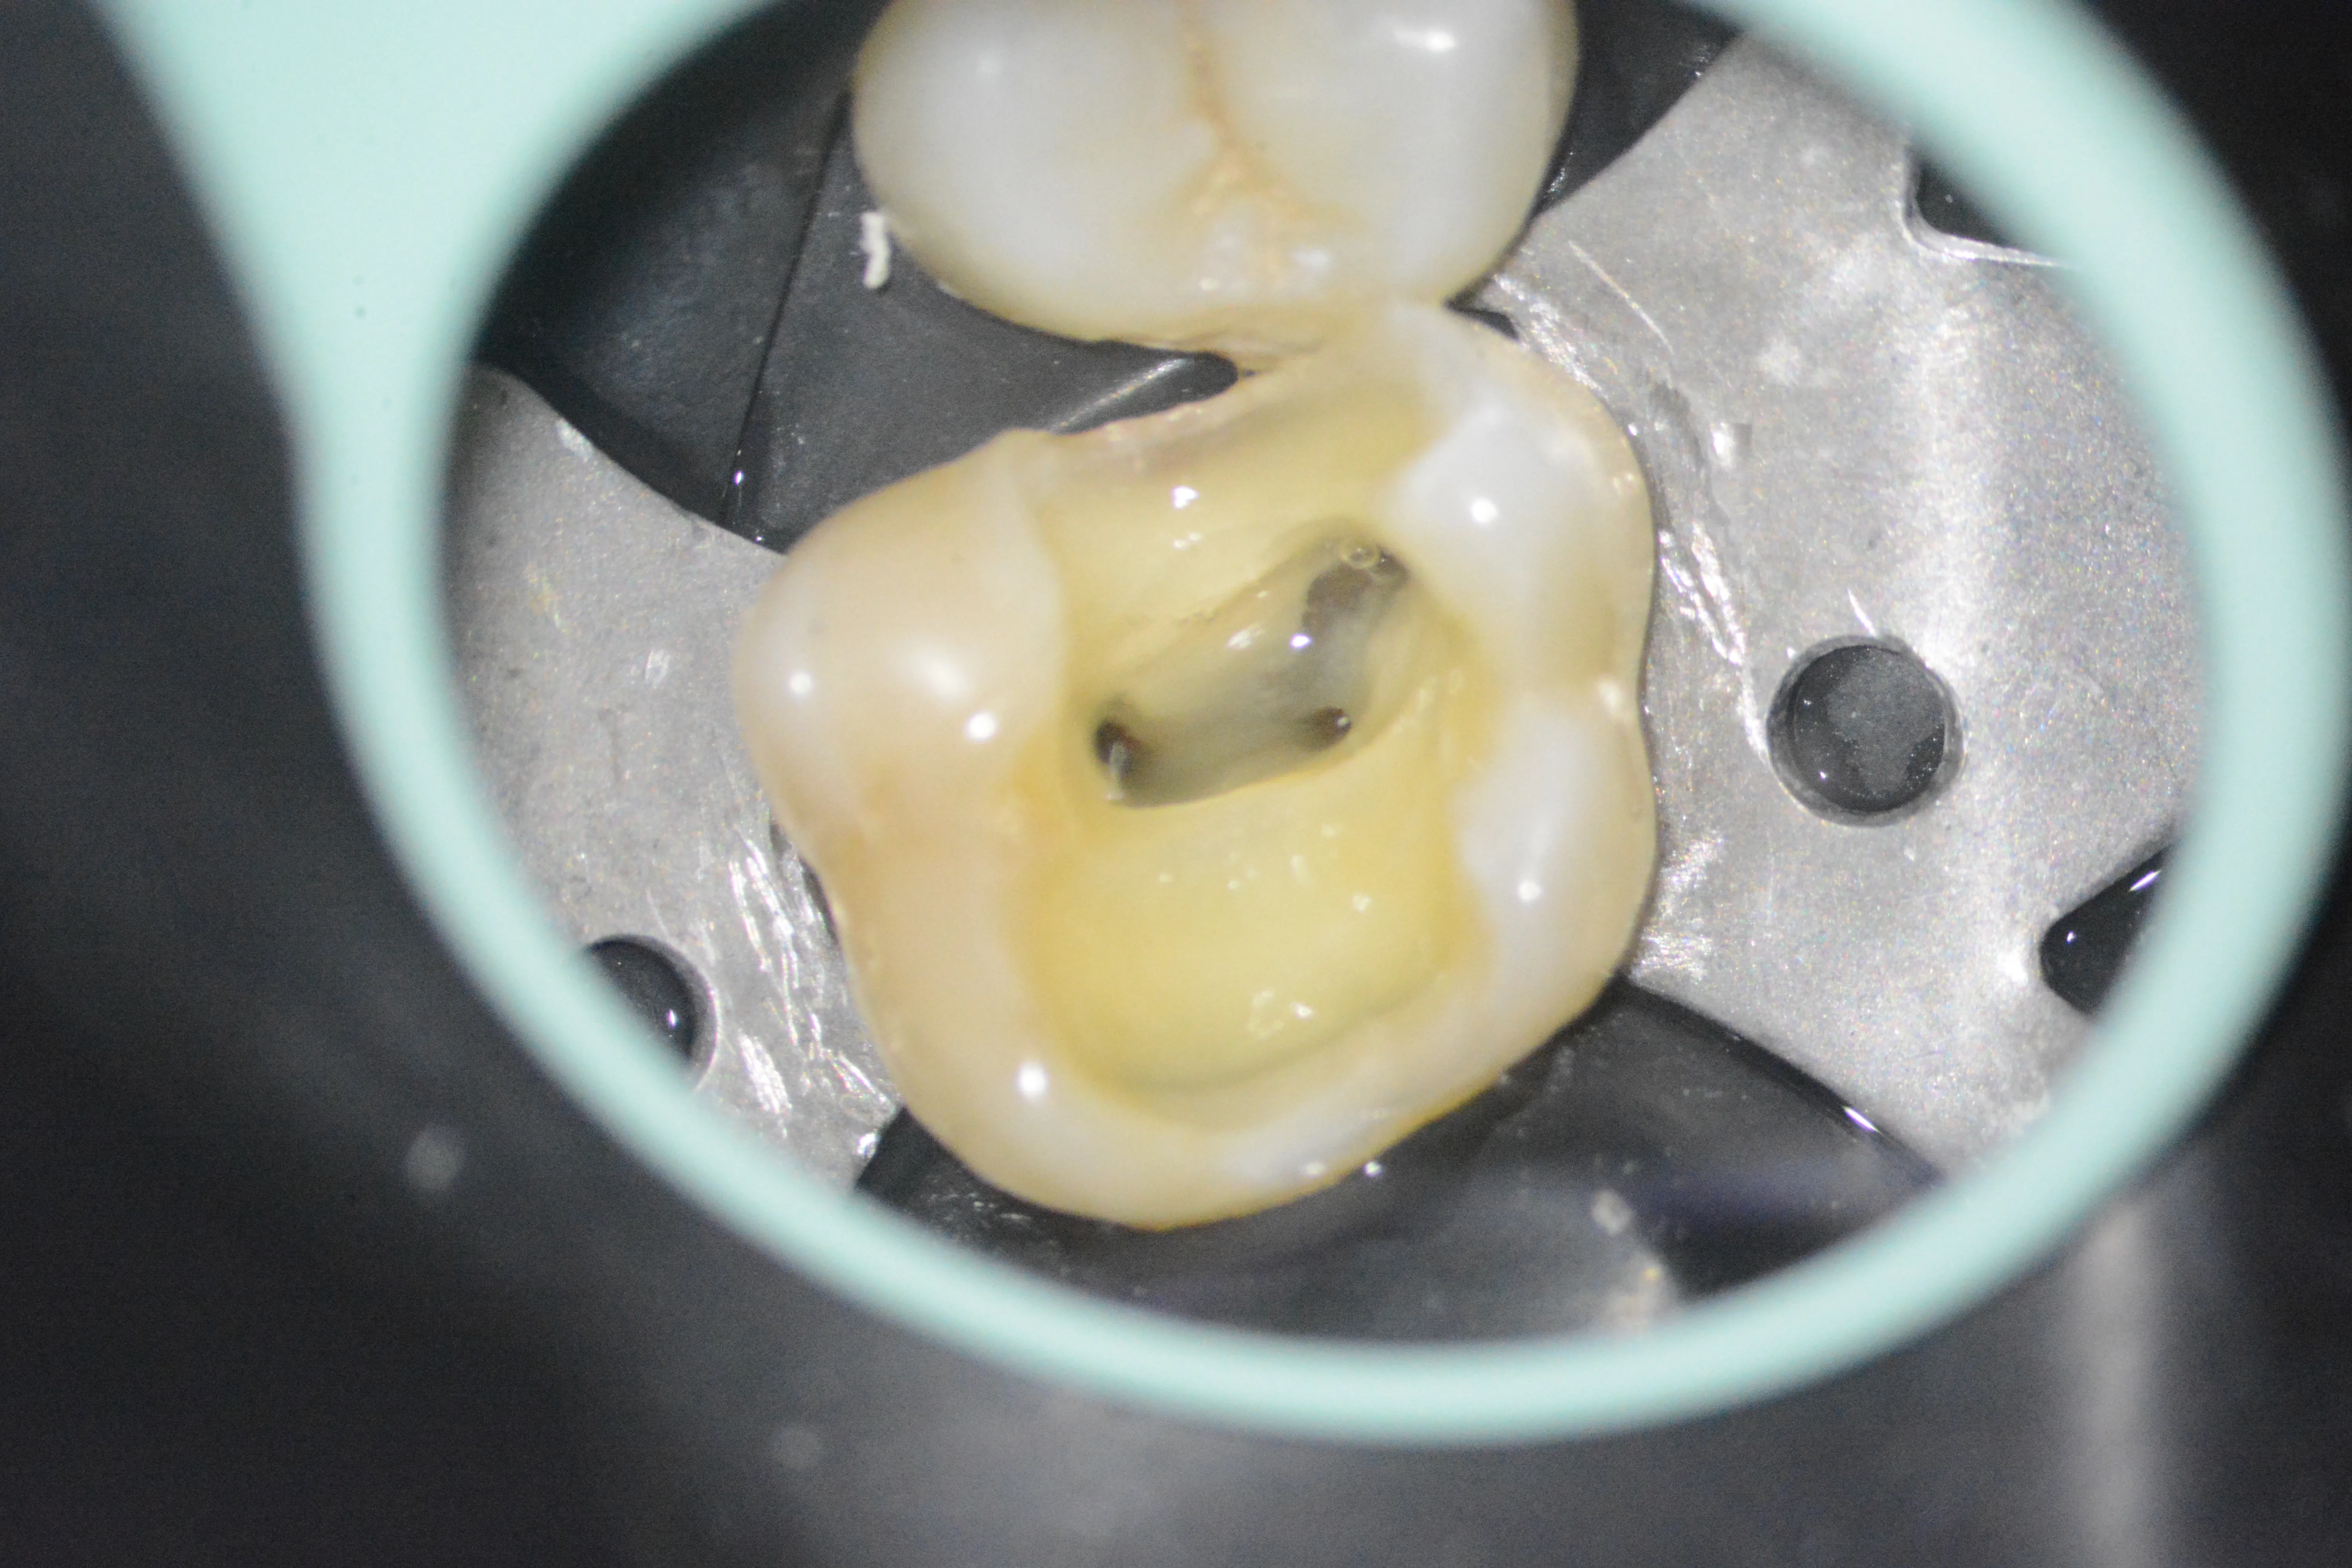

3 – Aspectul pulpei coronare